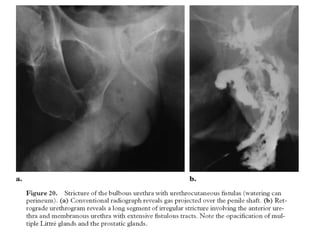

• Urethroperineal fistulas are most often the

consequence of a periurethral abscess. In

general, the initial abscess cavity contracts by

means of healing fibrosis, which leaves only

the narrow fistulous tract from the urethra to

the perineum.

• Consequently, urination usually occurs

through the perineal fistulas, which results in

the so-called “watering can perineum”.

• They are usually the result of tuberculosis and

schistosomiasis infections.